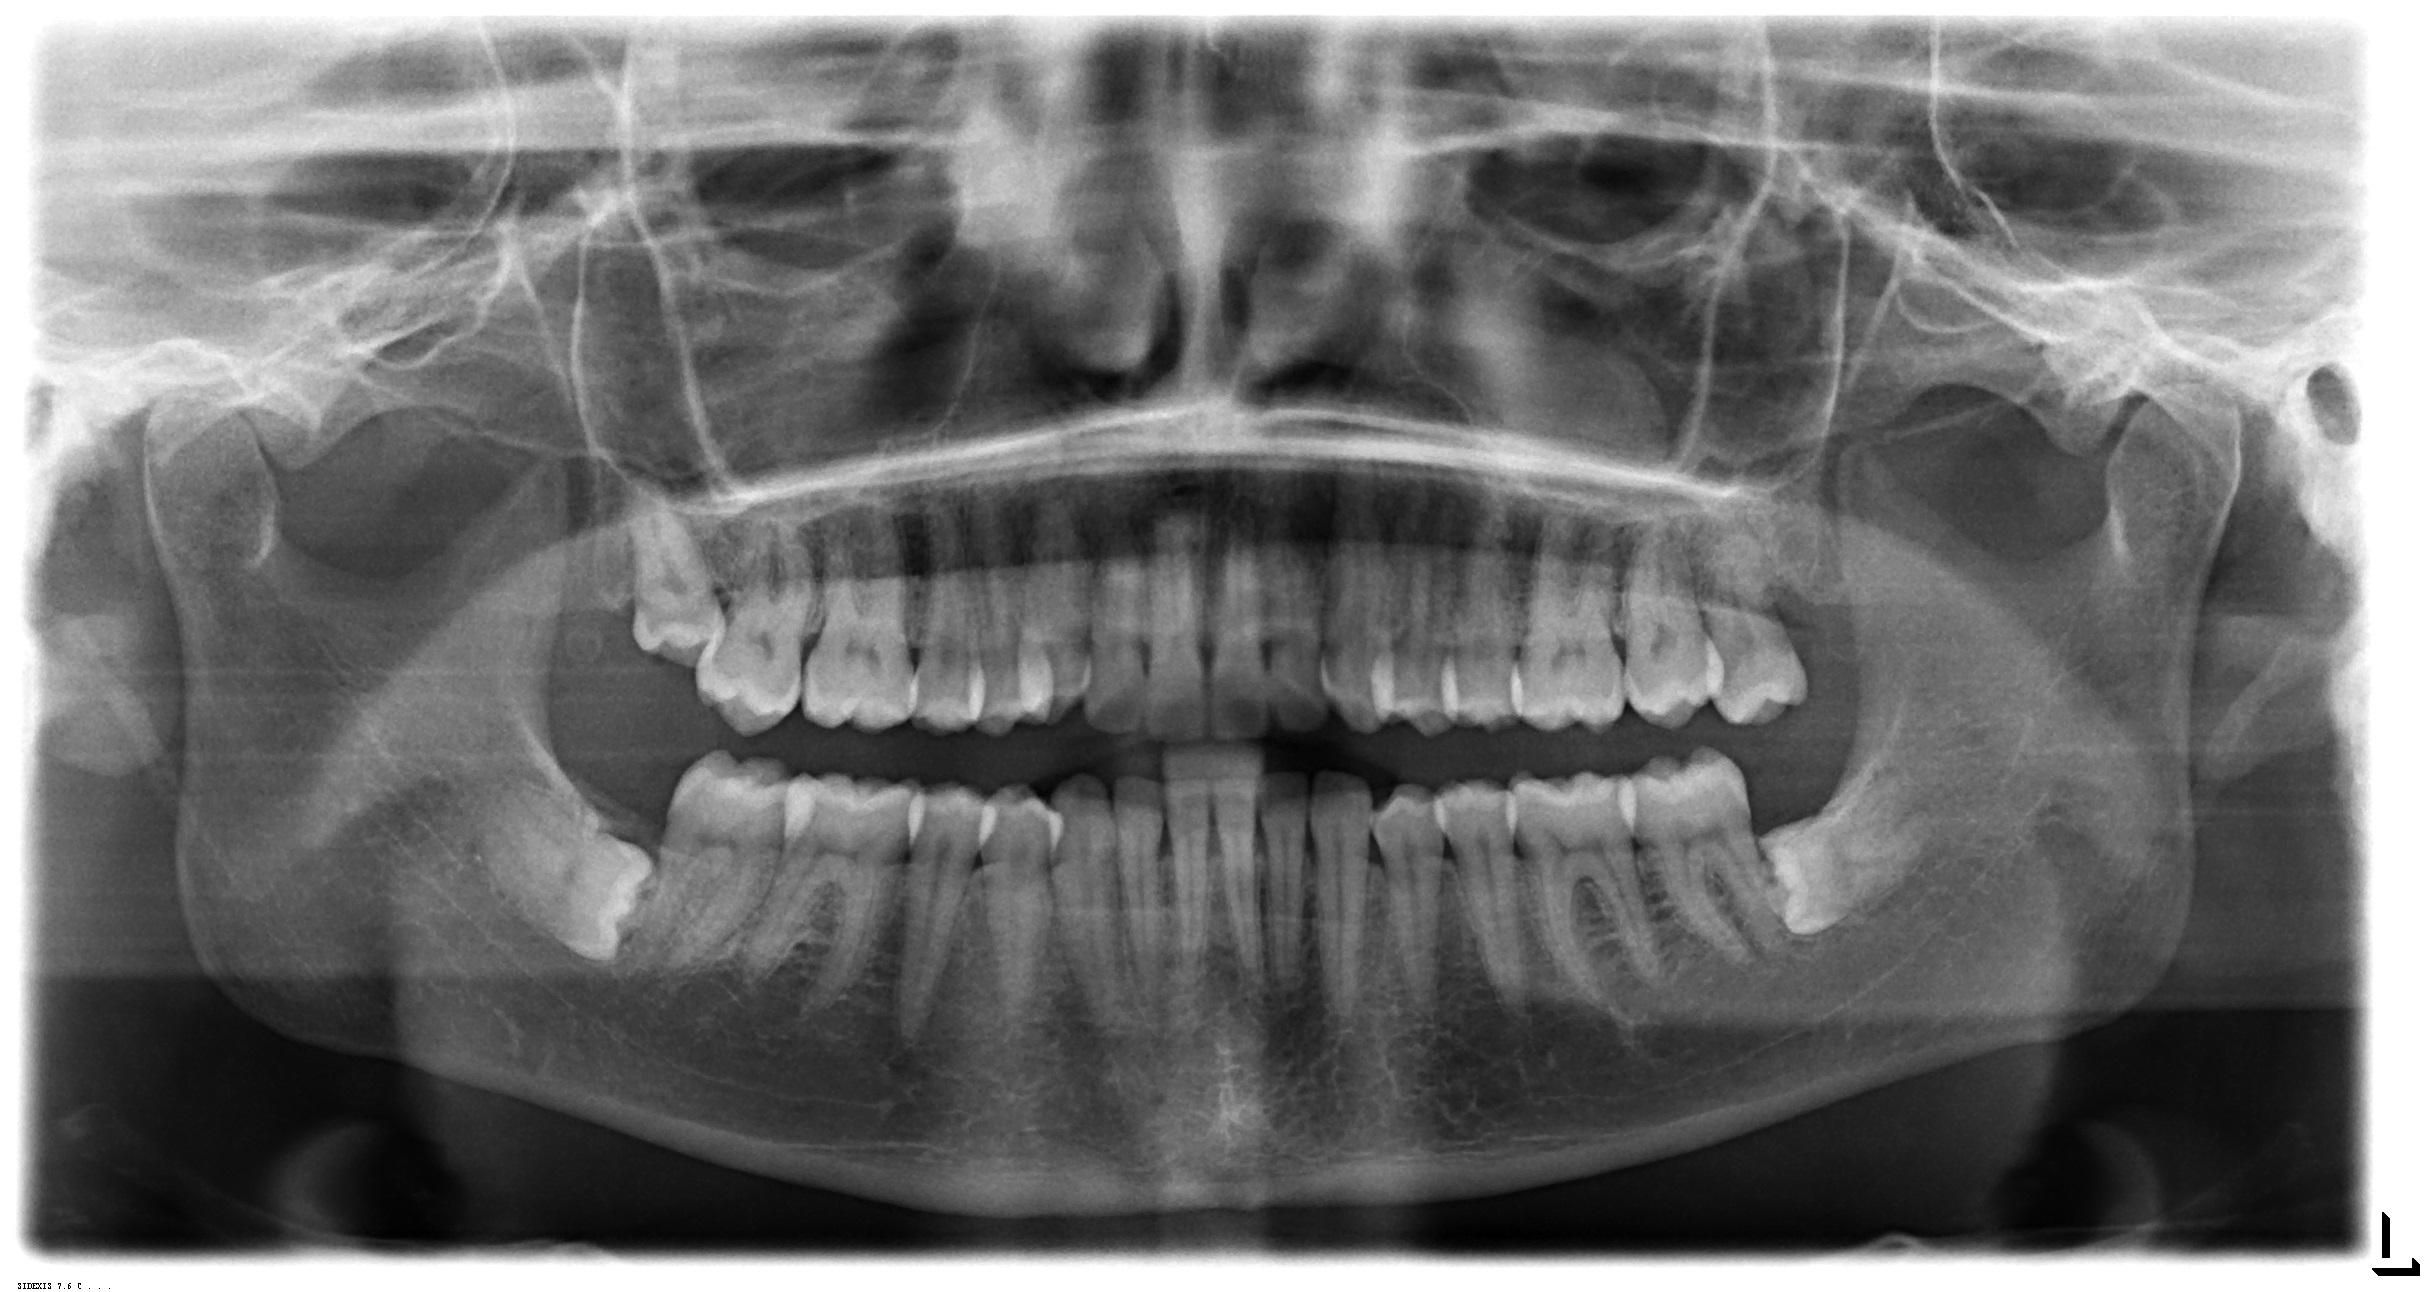

Faccio prima una lastra, e a distanza di due settimane una TAC Cone Beam.

Il referto del Radiologo per la Lastra:

Assenti gli ottavi superiori.

Disodontiasi di 38,48, ritenuti in inclusione osteomucosa, lievemente distoangolato e con apici radicolari che si proiettano sul rispettivo

canale mandibolare.

Lieve ipodiafania endoantrale declive destra.

Il referto del Radiologo per la TAC Cone Beam:

Disodontiasi di 38,48 in attuale ritenzione pressoché osteomucosa, lievemente distoangolati, entrambi con apici radicolari a diretto

contatto con il rispettivo canale mandibolare. Quest’ultimo decorre bilateralmente contatto con la forcazione radicolare bassa degli ottavi,

moderatamente improntato (parassiali destra 4-14; sinistra 16-22).

Si rimanda a deduzioni clinico specialistiche.

In via collaterale, piccola opacità interapicale 35-36 di presunta natura idiopatica. Utile confronto con precedenti radiografici.

Dalle radiografie non si evidenziano a carico dell’area superiore destra problemi di sorta. Probabilmente la storia un po’ tribolata ha creato qualche strascico che a mio avviso andrà a spegnersi lentamente.

Non escludo però, avendone avuto riscontro negli anni di professione, che i denti inclusi inferiori possano avere qualche responsabilità sui sintomi (almeno nel lato in cui avverte il problema). É probabile che prima o poi dovrà estrarli. Alla sua domanda su eventuali problemi sulle estrazioni, aggiungo che, come tutti gli atti chirurgici, un rischio esiste, ma nelle mani giuste è sicuramente trascurabile.